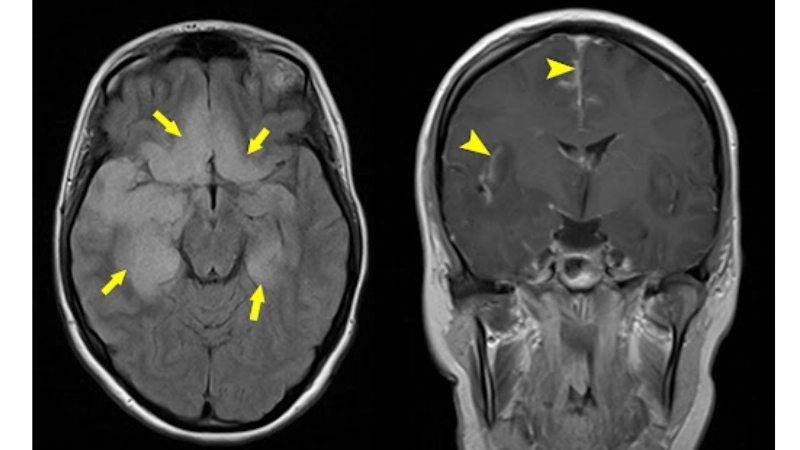

Image description of Herpes Simplex Encephalitis

Herpes Simplex Encephalitis is a rare but serious brain infection caused by herpes simplex virus. It leads to fever, headache, confusion, seizures, and potential long-term neurological damage. Early detection and treatment are crucial for recovery.

Encephalitis diagnosis needs MRI and lab tests